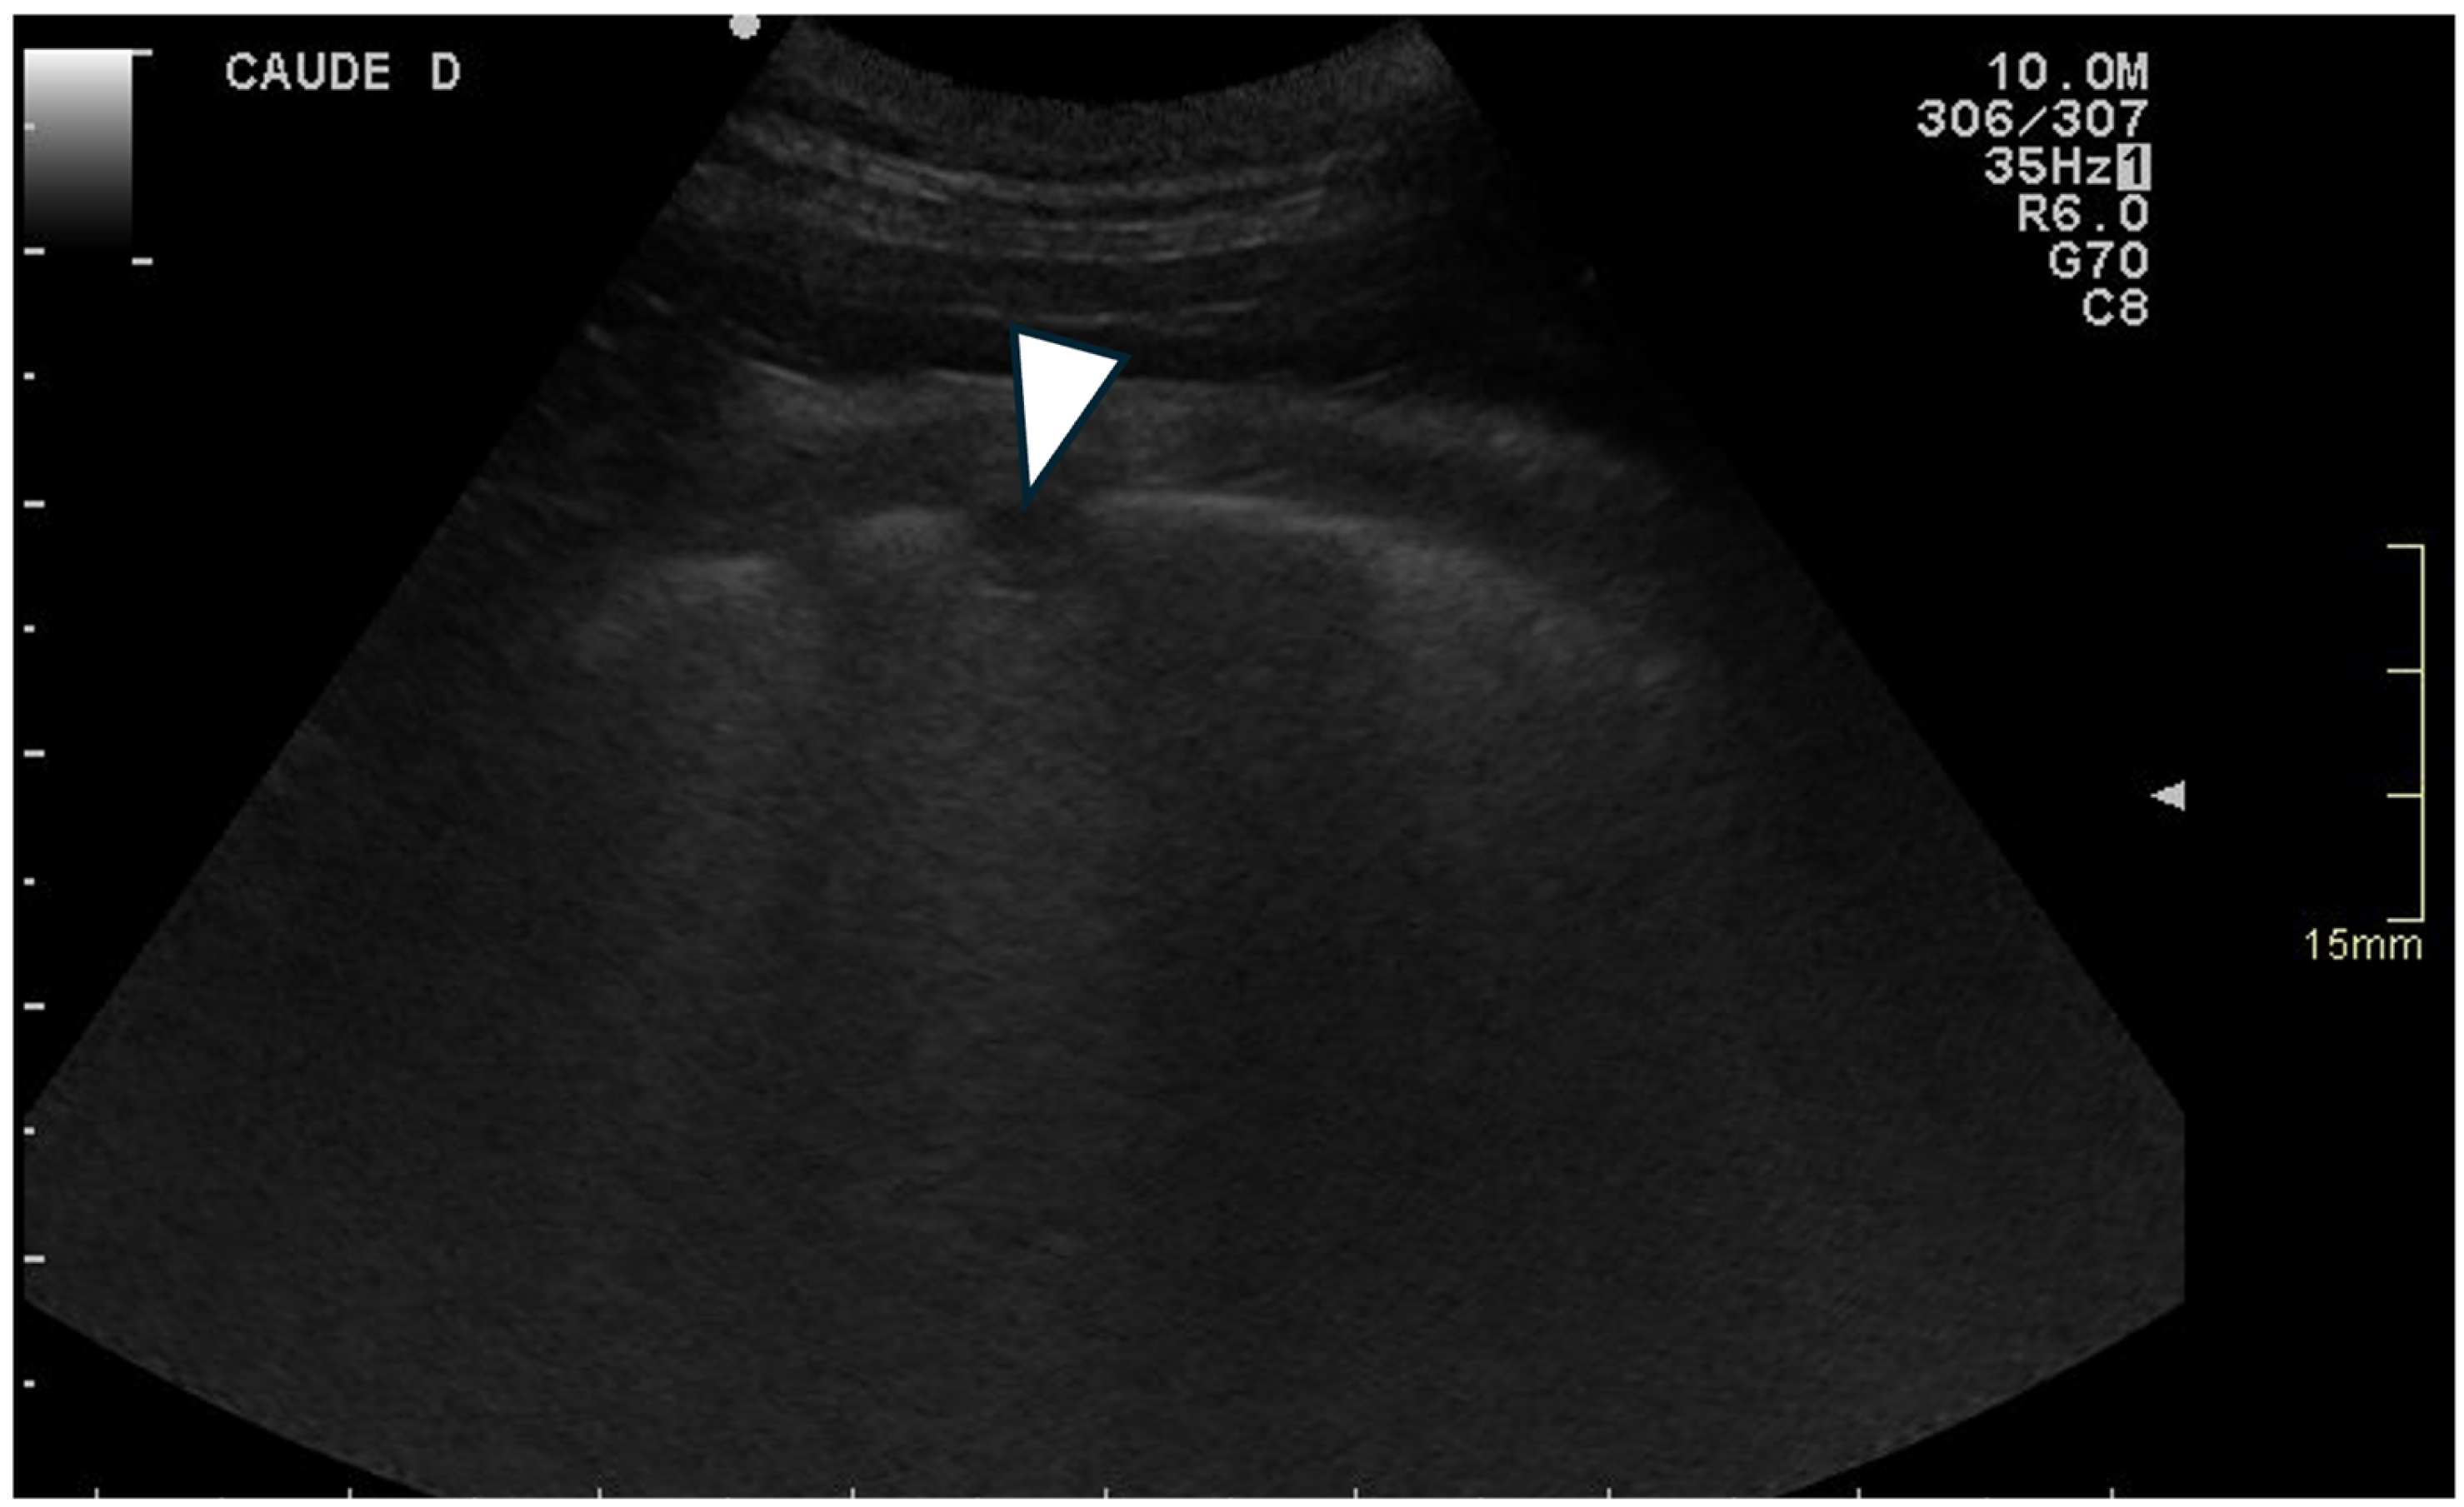

For each location, the presence and the number of ring-down artefacts (Figure 1) were counted. Depending on the number of artefacts, a score was obtained from 0 to 3 (Table 1). A similar method was applied for other lung lesions, such as peripheral hypoechoic pulmonary nodules or hypoechoic pulmonary areas (Table 1, Figure 2). The pleural surface was defined as smooth or irregular (Table 1, Figure 3)—scores of 0 or 1—and pleural sliding was assessed as present or absent (Table 1)—scores of 0 or 1. Pleural effusion was assessed as present or absent—scores 0 or 1 (Table 1). The scores were summed for each location and each side, and a total score out of 72 was attributed to each dog. Examinations were performed by the same operator (GB) on all dogs in a blinded fashion.

3.3.4. Pleural Surface

An irregular pleural surface was observed in 16 of the 17 WHWTs affected with CIPF and in 8 of the 10 control dogs (p = 0.26). No significant difference was observed regarding total score for irregular pleural surface between groups (median = 7, range = 0–8 in CIPF vs. median = 4.5, range = 0–8 in controls) (p = 0.057). There was no significant difference between groups regarding the median score for pleural surface irregularity per location (median = 1, range = 0–1, vs. median = 0.75, range = 0–1, respectively, p = 0.324). No preferential location for the lesions was observed.

Figure 3. Ultrasonographic image of the thorax of a control WHWT (A) and a WHWT affected with CIPF (B). (A): smooth pleural surface, (B): irregular pleural surface (white arrows). The images were obtained in a transverse orientation (parallel to the ribs).